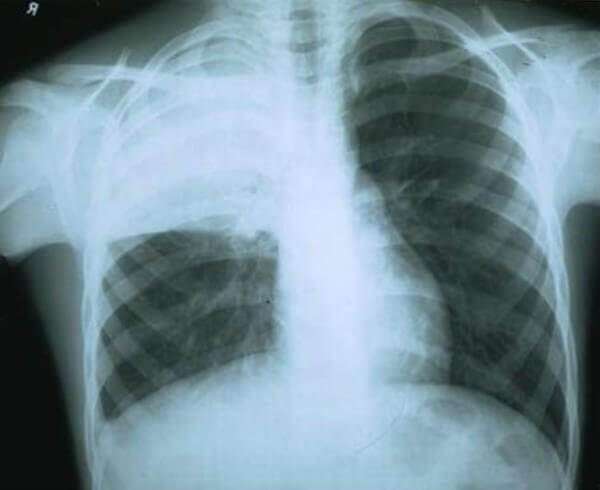

Крупозная или долевая

Данной форме характерно формирование больших участков поражения легочной ткани. Патологический процесс может охватывать как одно, так и оба легких. На иллюстрации ниже показана тяжелая форма крупозной пневмонии.